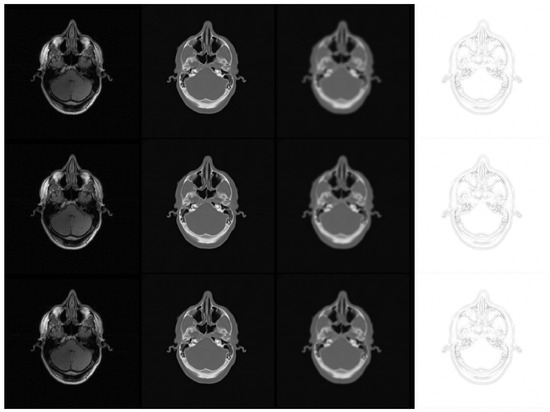

Metrics such as the structural similarity (SSIM) index, peak signal-to-noise ratio (PSNR), and mean-squared error (MSE) [51] provide quantitative measures for the similarity between two images. We used these to compare the synthetic CT images generated by our method to ground truth CTs. Table 1 shows the performance (mean and standard deviation of a five-fold cross validation) of the 2-D and 3-D models with respect to different training optimizers. Note that the higher the value of SSIM and PSNR, the better the performance, while the opposite is true for MSE. Figure 5 shows some example outputs for the different training optimizers.

Figure 5. Example results for synthetic CT generation. The first, second, and third rows represent SGDM, RMSProp, and Adam optimizers, respectively. Columns from left to right show the input MRI, corresponding ground truth CT, predicted CT, and the complement of the absolute difference image for each optimizer.